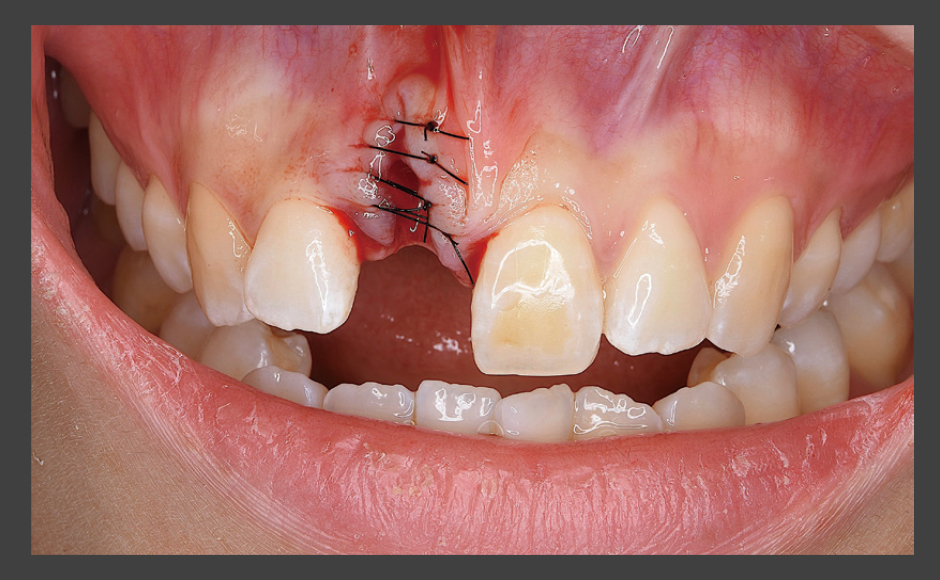

Astratech Implant System EVを使用した審美領域のインプラント治療

症例1:Socket Shield Technique(SST)を用いた審美領域のインプラント治療

症例2:硬軟組織のグラフトを施した審美領域のインプラント治療